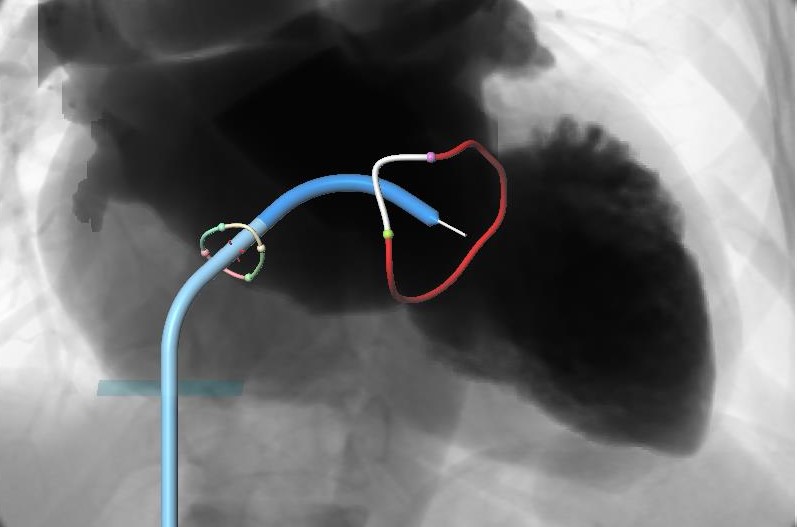

• Carillon Mitral Contour System (Cardiac Dimensions): Indirect annuloplasty device deployed in the coronary sinus to reduce annular dilation and improve mitral leaflet coaptation.

coronary_sinus.png